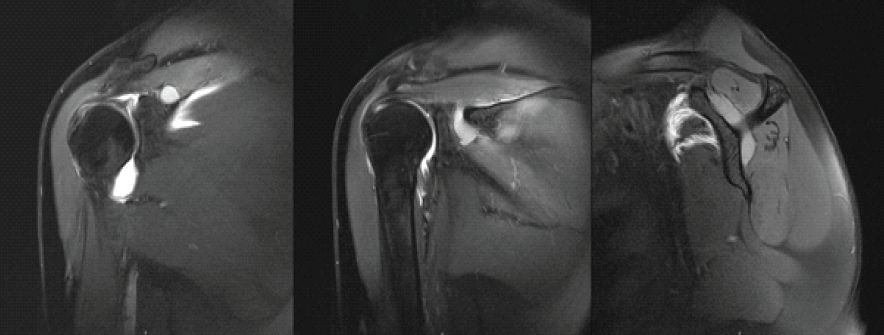

A 63-year-old right-handed woman with no relevant medical history presented with a 6-month history of continuous dull right shoulder pain, aggravated by lying on the affected side and associated with nocturnal pain. She reported functional limitations in overhead activities. Analgesics included paracetamol, ibuprofen, and topical diclofenac. Her regular physical activities included walking and cycling. Examination showed normal biceps and triceps reflexes, intact sensation, negative Spurling’s test, and preserved cervical and cervicodorsal mobility with negative facet joint and foraminal compression tests. Increased tone was noted in the postural muscles, mainly in the upper trapezius. Shoulder assessment revealed painless passive external rotation and abduction-external rotation, but active external rotation strength was reduced to 4/5 on the Medical Research Council scale. Impingement signs and Jobe’s test were negative. Palpation over the suprascapular notch elicited tenderness. Ultrasound revealed a cystic lesion posterior to the glenoid. Arthro-MRI confirmed a cyst from the spinoglenoid to the suprascapular notch along the course of the SSN. No teres minor atrophy was observed. Additional findings included insertional tendinopathy of the supraspinatus and a superoposterior labral tear. The imaging appearance was consistent with an intraneural ganglion cyst. Electromyography (EMG) showed a right SSN lesion at or proximal to the supraspinatus muscle branch, consistent with a partial axonotmesis and associated with moderate-to-severe muscular involvement. The patient initially opted for a conservative approach with physiotherapy, ultrasound-guided aspiration, and intralesional glucocorticoid injection for symptomatic relief (Depo-Medrol 80 mg). Aspiration of the cyst was attempted. However, only 1 mL of the thick mucinous fluid could be retrieved. At 4 weeks, pain improved but there was persistent fatigue with overhead activity and weakness in both the supraspinatus and infraspinatus. Ultrasound showed a persistent anechoic, lobulated cyst (9.4 × 7.6 mm) in the suprascapular notch, with extension to the spinoglenoid (4.1 × 7.4 mm) notch, without hyperemia. Physiotherapy was continued, with follow-up planned in 2 months. Two months later, ultrasound showed enlargement at the suprascapular notch (11.4 × 9.3 mm) and a stable size at the spinoglenoid notch (4.0 × 7.3 mm) (Fig. 2). EMG revealed improved compound muscle action potential (CMAP) amplitude and recruitment in the supraspinatus, but decreased recruitment and denervation in the infraspinatus. A surgical indication was made for arthroscopic decompression of the cyst at both the suprascapular and spinoglenoid notches and treatment of the labral tear. Arthroscopy revealed a degenerative type IIB superior labrum anterior to posterior (SLAP) lesion, treated with biceps tenotomy and labral debridement, as repair was deemed infeasible. Cyst decompression exposed a well-defined synovial cyst wall surrounding the nerve. Incision released a wine-red mucinous fluid, and the wall was carefully debrided to achieve complete decompression (Fig. 1)

Figure 1: Magnetic resonance imaging of the right shoulder. This figure illustrates cystic formation at the suprascapular notch (left), the spinoglenoid notch (middle), and the tubular connection between the two (right).